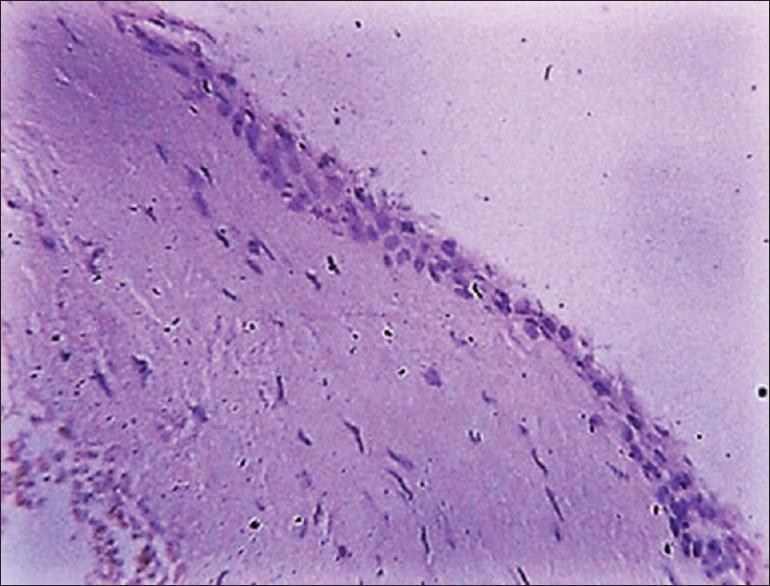

A total of eighty cases, in which twenty cases each of ameloblastoma, unicystic ameloblastoma, dentigerous cyst, and odontogenic keratocyst (OKC) were included in the study. Slides were made from the archival blocks of each case and were stained immunohistochemically with calretinin.

Correlation between calretinin staining and histopathological diagnosis was done, and it was found that all twenty cases of ameloblastoma showed positivity for calretinin, whereas 17 of twenty cases of unicystic ameloblastoma showed positivity for calretinin staining. All the cases of OKC and dentigerous cyst were negative for calretinin.

对钙视网膜蛋白染色与组织病理学诊断之间进行相关性分析,发现所有20例成釉细胞瘤病例钙视网膜蛋白呈阳性,而20例单囊性成釉细胞瘤病例中有17例钙视网膜蛋白染色呈阳性。所有OKC和含牙囊肿病例钙视网膜蛋白均为阴性。